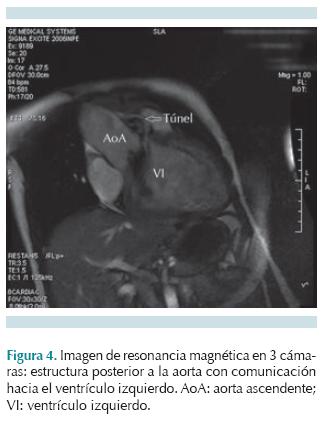

Los datos clínicos suelen evidenciar un soplo sistolodiastólico en foco aórtico, con frémito e irradiación a hueco supraesternal, acompañado de pulsos amplios. En pacientes mayores los síntomas pueden ser similares a una estenosis valvular aórtica; sin embargo, se asemejan más a los de una insuficiencia valvular aórtica con alteraciones en la presión arterial sistémica. La gravedad de los síntomas es variable y los pacientes pueden permanecer asintomáticos por años, hasta desarrollar insuficiencia cardiaca con descompensación súbita y muerte. Los estudios de gabinete iniciales son electrocardiograma y radiografía de tórax en proyección posteroanterior, que muestran datos de hipertrofia ventricular izquierda, pueden indicar datos de sobrecarga diastólica y cardiomegalia con dilatación de aorta ascendente, respectivamente. La ecocardiografía transtorácica es la prueba diagnóstica de elección: en eje largo paraesternal y eje corto demuestran el túnel con dilatación de la aorta ascendente. En Doppler color se observa flujo diastólico originado a nivel de la unión sinotubular alejándose hacia el ventrículo izquierdo. Los túneles que se abren hacia el ventrículo derecho se visualizan en el eje corto paraesternal de la válvula aórtica, mientras que la función del ventrículo izquierdo, que es afectada de forma variable con hipertrofia y dilatación, se evalúa en la vista paraesternal eje corto a nivel de los músculos papilares.3 En casos no concluyentes, en los que no se puedan demostrar con claridad las arterias coronarias, se puede requerir angiografía con catéter. Con estudios avanzados como la resonancia magnética también se pueden demostrar los túneles aorto-ventriculares derecho o izquierdo. El diagnóstico diferencial incluye defecto septal ventricular con lesión valvular, doble lesión aórtica, aneurisma o rotura del seno de Valsalva.

Los estudios de gabinete mostraron en la radiografía de tórax cardiomegalia y crecimiento de los perfiles derecho e izquierdo (Figura 1). El electrocardiograma mostró hipertrofia ventricular izquierda y sobrecarga de volumen en precordiales izquierdas. El ecocardiograma transtorácico en eje largo paraesternal mostró un flujo que se originaba a nivel de la coronariana derecha y se presenta durante la diástole con dirección hacia el ventrículo izquierdo, anillo valvular aórtico dilatado con protrusión hacia el ventrículo izquierdo (Figura 2A). En el ecocardiograma en eje corto paraesternal en modo bidimensional y Doppler color se observó el anillo aórtico dilatado con flujo diastólico entre coronarias derecha e izquierda (Figura 2B). En una vista supraesternal de eje largo se observó una inversión holodiastólica del flujo en la aorta descendente, una pendiente de desaceleración mayor de 3.5 m/s2 en un eje apical 5 cámaras, y un diámetro diastólico y sistólico con Z score +6.1 que confirmaron dilatación ventricular por insuficiencia aórtica. Por este método no fue posible definir la anatomía de las arterias coronarias y, ante duda de túnel aorto-ventricular izquierdo versus aneurisma roto de seno de Valsalva, se decidió realizar cateterismo cardiaco que mostró patrón coronario normal y en un aortograma en incidencia oblicua anterior derecha donde se observó una estructura vascular externa originada en la raíz de la aorta, que correspondía a un túnel aorto-ventricular. La presión telediastólica del VI fue de 21 mmHg (Figura 3). La resonancia magnética apoyó el diagnóstico de túnel aorto-ventricular izquierdo al observarse una comunicación a nivel de la unión sinotubular hacia el ventrículo izquierdo durante la fase diastólica (Figura 4). Se inició tratamiento anticongestivo y se llevó a cirugía donde se encontró una válvula aórtica bivalva, engrosada y con prolapso, túnel aorto-ventricular entre la comisura de las valvas coronarianas derecha y la izquierda, ligeramente por debajo de la unión sinotubular. Se colocó parche tratado con glutaldehido en el extremo aórtico del túnel y una prótesis valvular aórtica tipo St. Jude 25 mm. El paciente permanecía asintomático a los 22 meses de la cirugía.